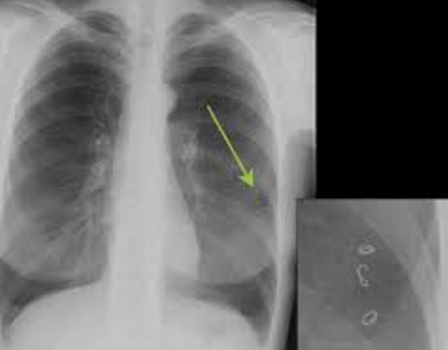

К сожалению, обнаружить поражение на ранних этапах возможно только с помощью рентгенографии легких. Дополнительными методами могут быть компьютерная томография и УЗИ, лапароскопия и серологические исследования.

Подтверждение диагноза, а также его отличие от туберкулеза или рака легких, могут быть осуществлены с помощью иммуноферментных исследований и реакции непрямой гемагглютинации.